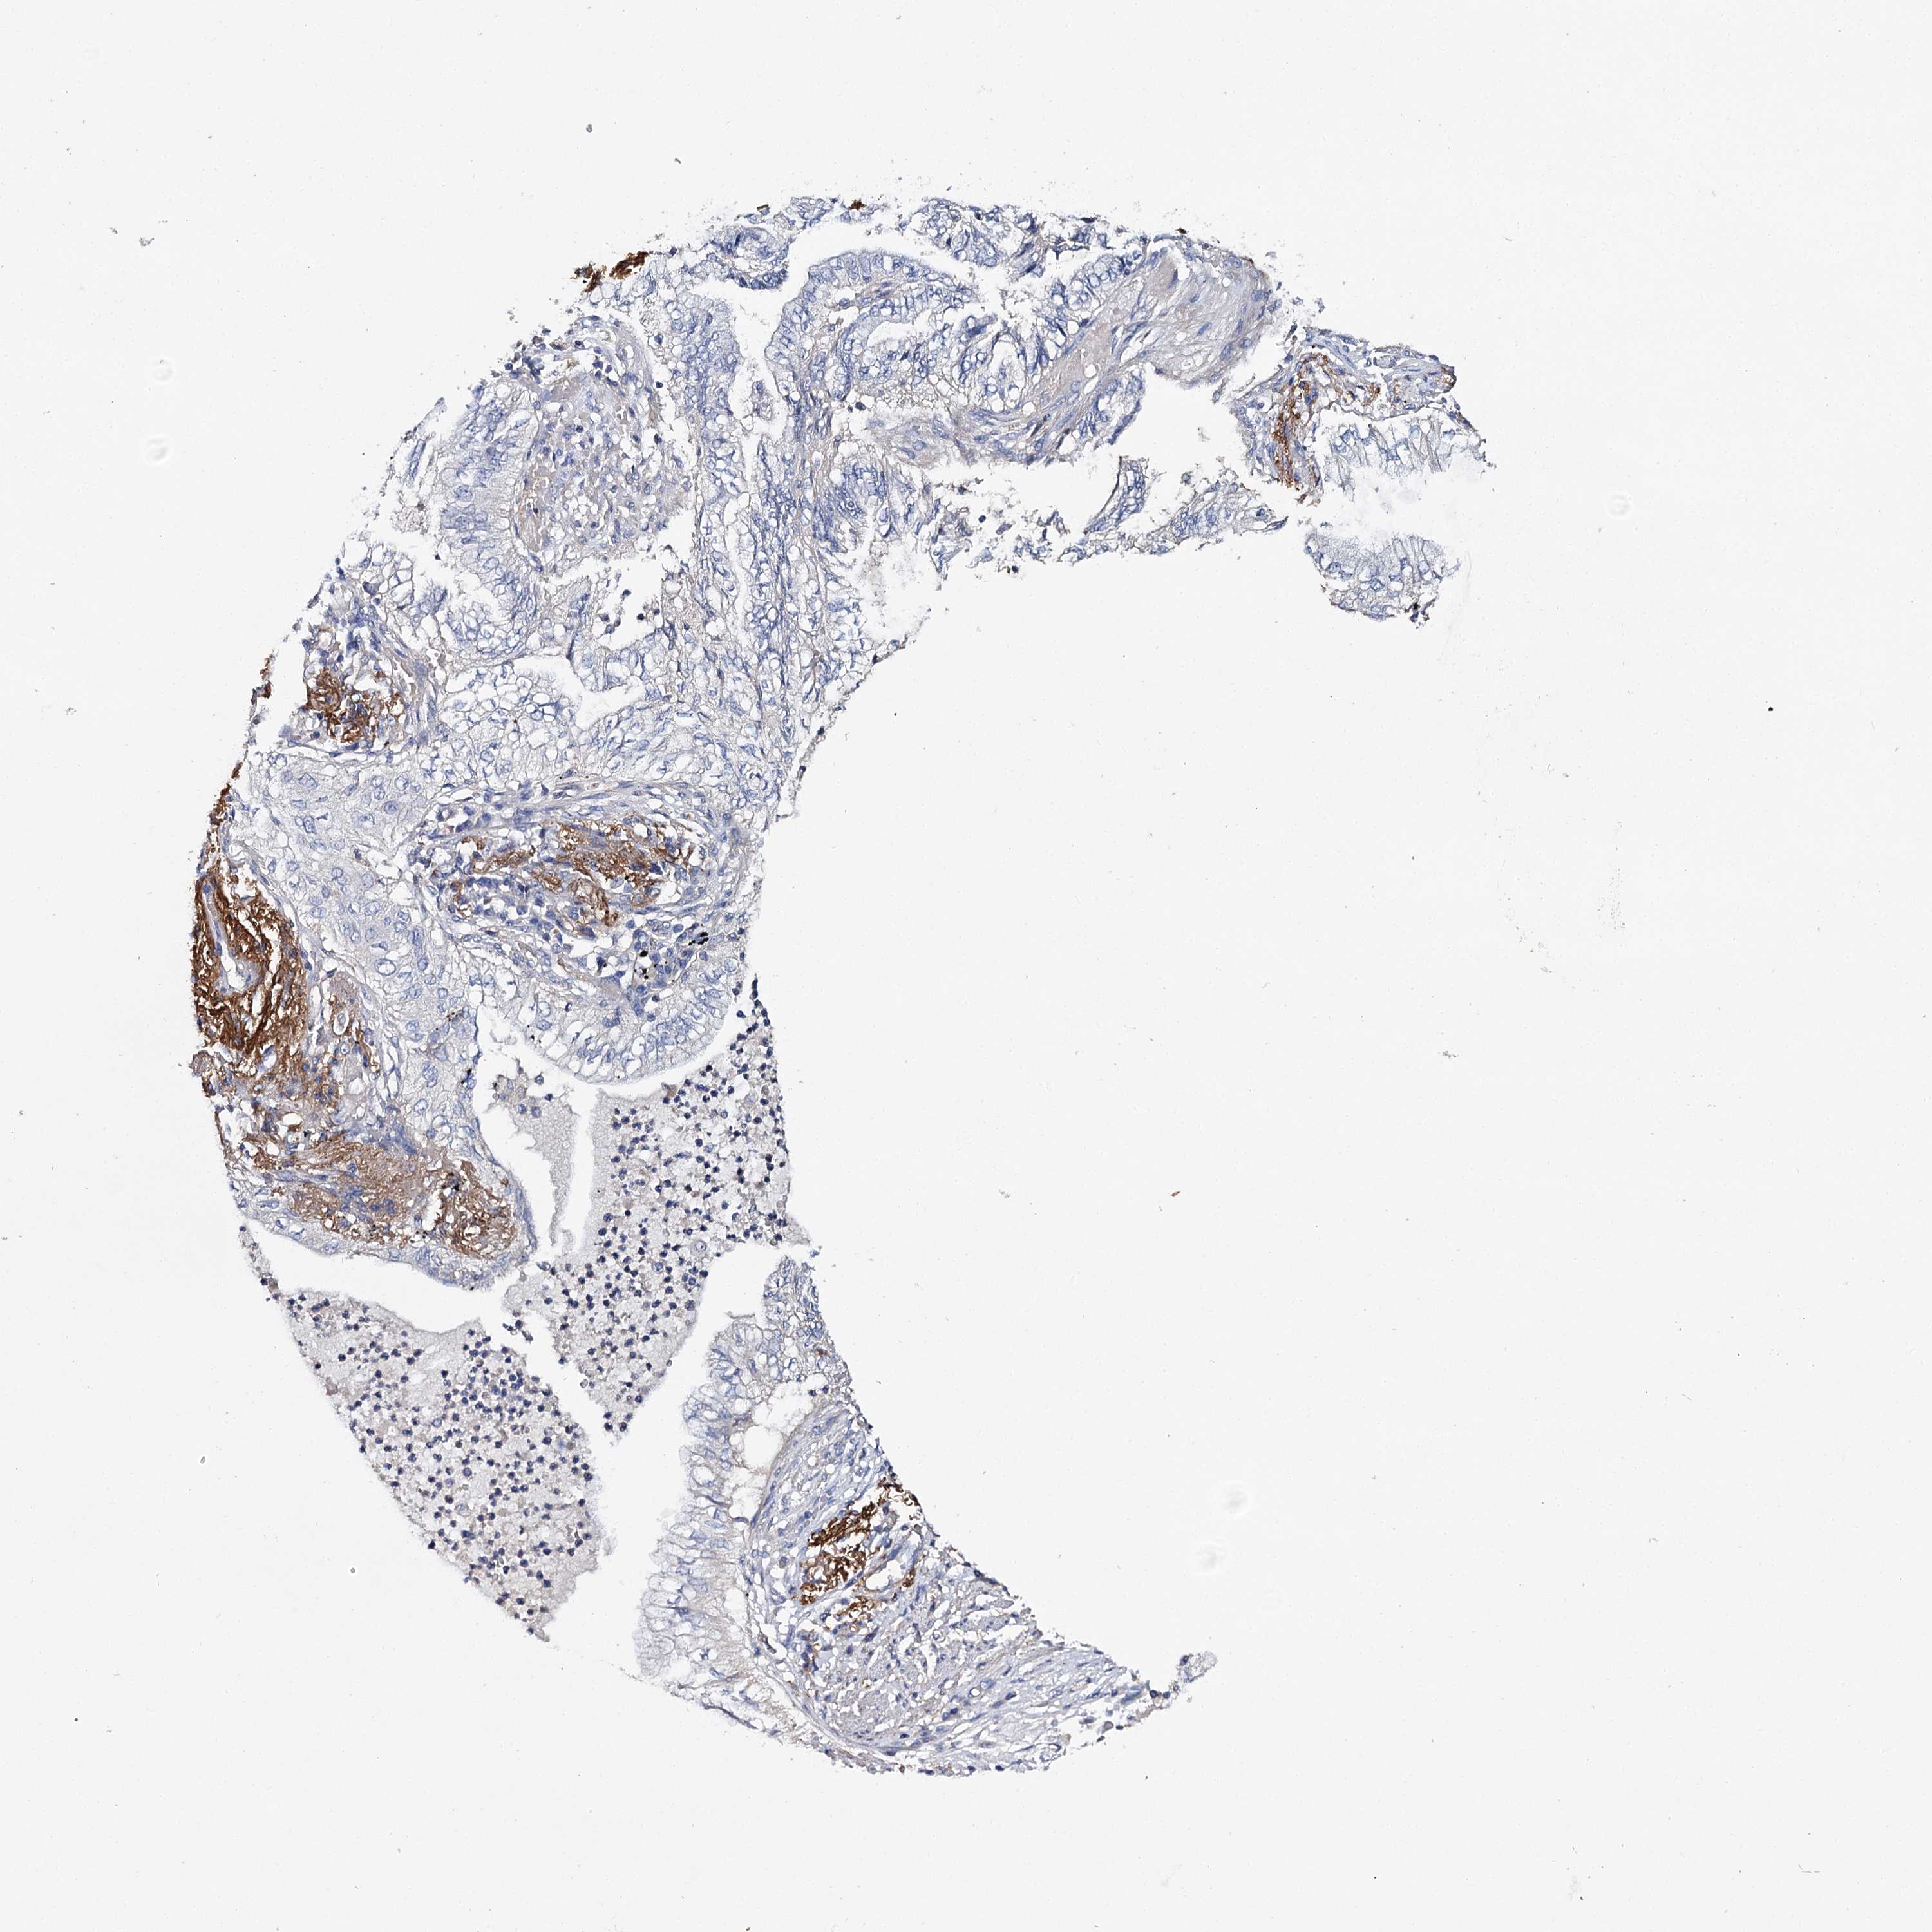

CANCER LUNG CANCER Show tissue menu

LUAD TCGA LUAD VALIDATION LUSC TCGA LUSC VALIDATION PROTEIN LUAD CPTAC PROTEIN LUSC CPTAC PROTEIN EXPRESSION

ANTIBODIES

AND

VALIDATION